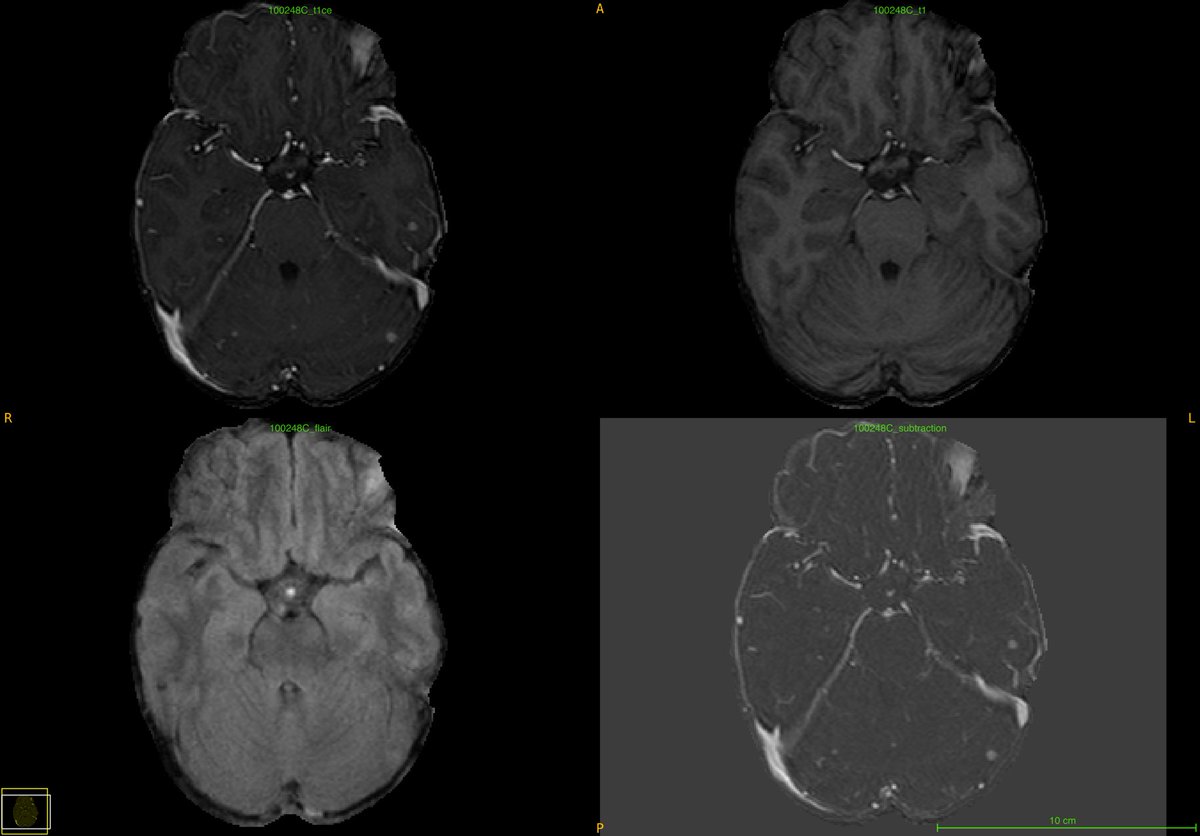

@BraTS_challenge meets @ConnectomeStud1! Celebrating our two top annotators as they receive their certificates and exclusive Yale merchandise from @MariamAboian. Gearing up for BraTS 2024 with both pre and post-treatment cases! @moawad_w @SpyridonBakas @ujjwalbaid0408